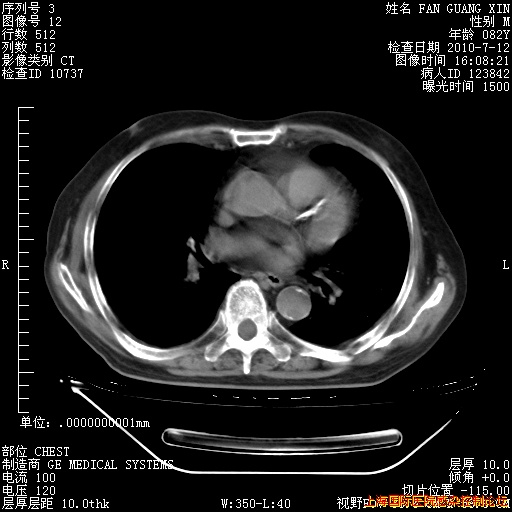

今天复查CT

今天CT

整整相隔30天的肺部CT好像有所好转啊。甲强龙减量第3天,需要观察体温。